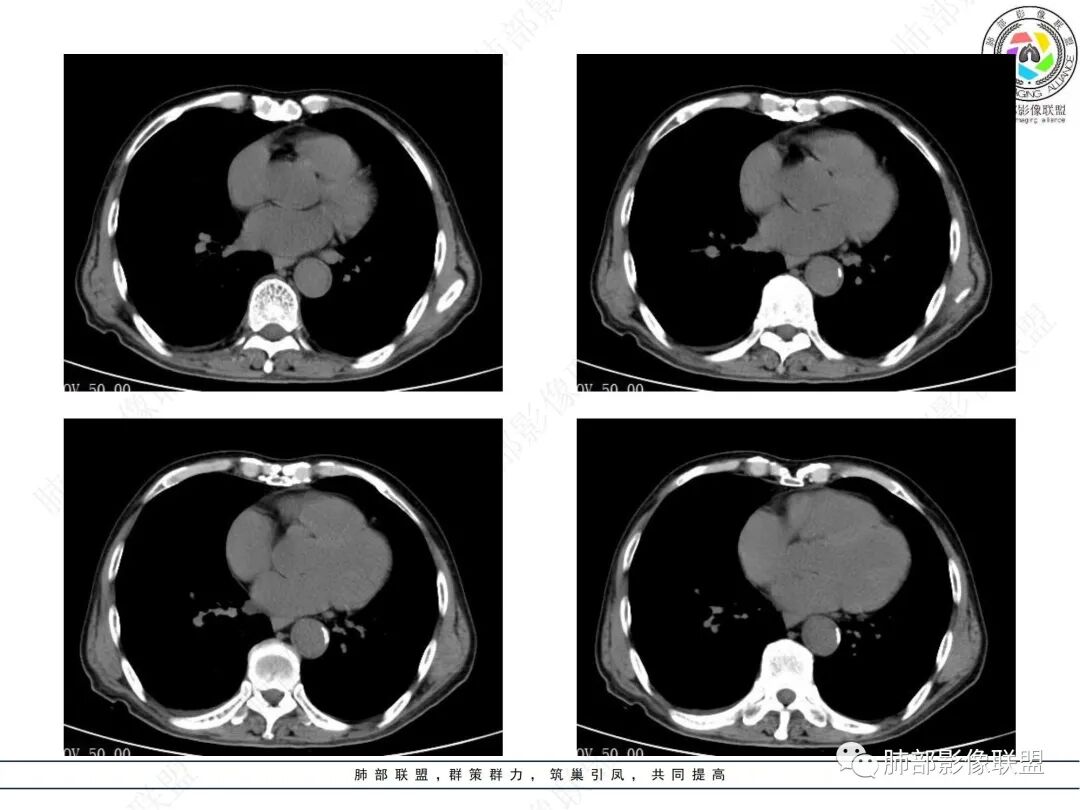

病理结果

治疗前后对比CT:

放线菌病